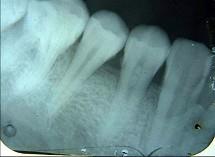

以下哪一项是诊断牙髓钙化的主要手段 ( )

A电活力测验

B视诊

CX线片检查

D温度测验

E光纤透照